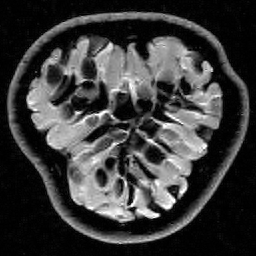

Having identified a measurement matrix to exploit structured sparsity, let us demonstrate its effectiveness. In Figure 5 we compare these measurements with the case of random Bernoulli measurements (this choice was made over random Gaussian measurements because of storage issues). As is evident, at all resolutions we see a significant advantage, since the former strategy exploits the structured sparsity. Note that for both approaches, the reconstruction quality is resolution dependent: the error decreases as the resolution increases, due to the increasing sparsity of wavelet coefficients at higher resolutions. However, because the Fourier/wavelets matrix is asymptotically incoherent (see also Section 4.1), it exploits the inherent asymptotic sparsity structure (6) of the wavelet coefficients as the resolution increases, and thus gives successively greater improvements over random Bernoulli measurements.

Recall that in type I problems such as MRI, we are constrained by the physics of the device to take Fourier measurements. A rather strange conclusion of Figure 5 is the following: compressed sensing actually works better for MRI with the intrinsic measurements, than if one were able to take optimal (in the sense of the standard sparsity-based theory) random (sub)Gaussian measurements. This has practical consequences. In MRI there is actually a little flexibility to design measurements, based on specifying appropriate pulses. By doing this, a number of approaches HaldarRandomEncoding ; ToeplitzMRI ; VanderEtAlSpreadSpectrum ; SebertRandomMRI ; WongMRI have been proposed to make MRI measurements closer to uniformly incoherent with wavelets (i.e. similar to random Gaussians). On the other hand, Figure 5 suggests that one can obtain great results in practice by appropriately subampling the unmodified Fourier operator.